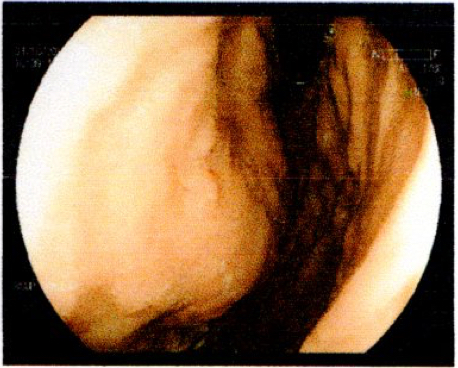

Gastric abnormalities show nonspecific gastrointestinal symptoms and similarly radiological findings. Intra and extra luminal gastric wall thickening are the most common finding in benign and malignant pathologic process. This aim of this case report was to describe several characteristics such as the location and size of the lesion, involvement of the gastric wall and surrounding structures, calcifications, and contrast enhancement pattern which can assist in radiological diagnosis. Several cases at our institution have similar gastrointestinal complaints, however, there were different lesions characteristic found in contrast enhanced abdominal CT scan. The first case 72-years-old man experienced hematemesis with radiologic finding diffuse gastric mucosal thickening as well as homogenous contrast enhancement but without calcification. The second case 37-years-old man complaint dizziness and melena with radiologic finding large tumor more than 10 cm in size, amorph calcification and heterogenous contrast enhancement. The last 60-years-old man case experienced melena and hematemesis, from abdominal CT scan showed irregular gastric mucosal thickening with heterogenous contrast enhancement and fat stranding around the lesion, without calcification. Methods used in these cases were contrast-enhanced abdominal CT scan, esophagogastroduodenoscopy (EGD), and biopsy in order to determine the diagnosis. Contrast-enhanced abdominal CT scan plays a vital role in describing the lesion characteristics which affects the determination of treatment options and future prognosis.